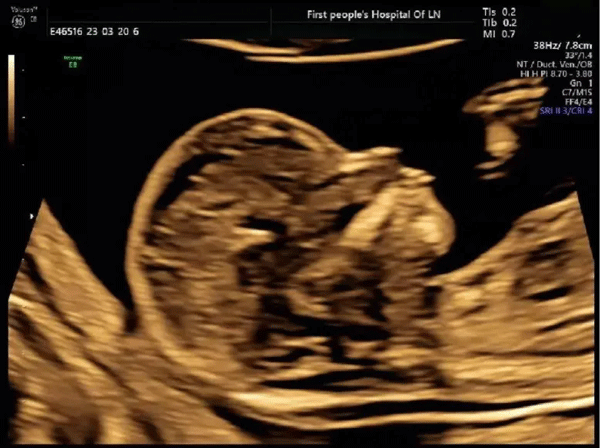

01、胎儿颈部透明带检查(NT检查)

免费为妊娠11-14周的孕妇提供一次超声胎儿颈部透明带检查(NT检查)。